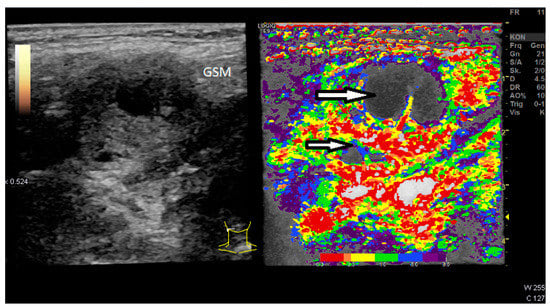

| CCDI incl. B-Flow | Vascularization pattern | - |

| CEUS | Perfusion and enhancement dynamics (Wash-in/Wash-out) | Time–Intensity Curve analysis with Time-to-Peak and Area-under-the-Curve; two ROI in the center, four at the margin of the LN and two in the surrounding soft tissue (outside of vessels). For the correct placement of ROI, only positive values were accepted (adjustment for artefacts). The diameter of each ROI was 2–3 mm. Additionally parametric evaluation of the perfusion kinetics. |